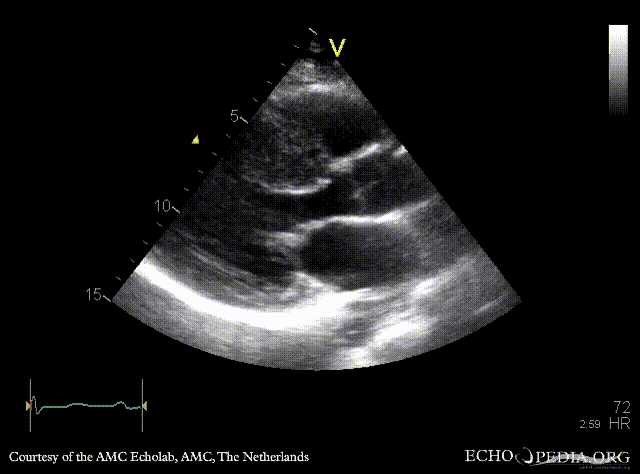

E00515.gif E00516.gif

A4CH: systolic obliteration of left ventricle, SAM of AMVL A4CH with Color Doppler: high velocity turbulent flow in LVOT and in the middle of left ventricle